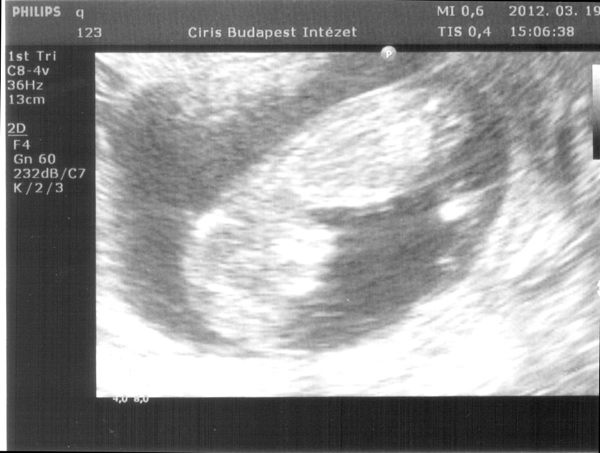

Ja Suti vicces, mert az en ferjem akarja az ikreket nagyon, es egy honapja mondom neki, hogy nem lesznek ikrek ,mert csak egy petesejt erik spontan ciklusban, erre kijovok es mondom neki, hogy kepzeld ketto is erik. O meg: na ugye hogy megmondtam, hogy ikreim lesznek. Bolond ember na